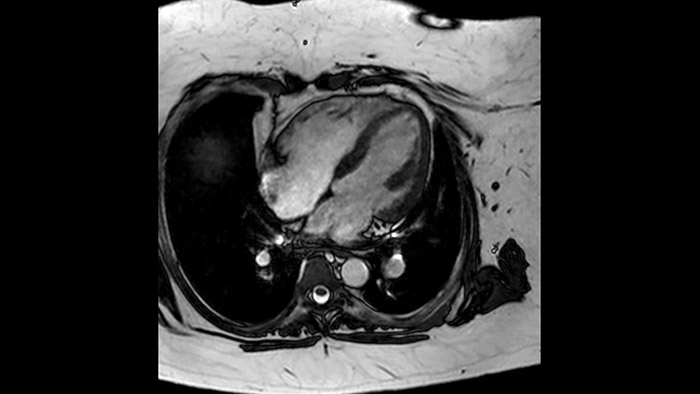

A utilidade do diagnóstico e prognóstico da RM cardíaca está a aumentar. Avalie a anatomia e função do coração utilizando aquisições cine, adquira informações sobre a perfusão e viabilidade do tecido cardíaco, visualize potenciais edemas com sequência de sangue escuro, aceda e quantifique mesmo a caracterização do tecido com a CardiacQuant.

Os diagnósticos tradicionais não têm a visibilidade necessária para ver os efeitos do tratamento cardíaco ou para detetar disfunção antes que os sintomas ocorram. Ao combinar a sequência de aquisição de RM da Philips Fast-SENC com a ferramenta de análise MyoStrain da Myocardial Solutions, as alterações precoces e subtis da função cardíaca podem ser medidas diretamente.